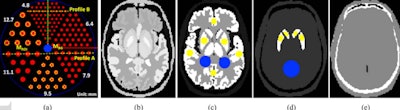

At the heart of the new design is a variable-aperture ring geometry (small detector modules moving radially in and out) that would allow the researchers to image subjects within the field of view in high resolution in all possible angular positions. Their system comprises eight large-area CZT detectors, as opposed to conventional SPECT systems with two-head Anger detectors.

"Our design feature includes a variable-aperture full-ring geometry to overcome the limited field of view and independently swiveling detectors to minimize the interference between each detector," Seo explained.

To evaluate the imaging performance of their proposed SPECT-CZT system, they used digital phantoms and realistic digital brain phantoms for conventional SPECT systems with comparable pixel sizes and radii of rotation. The proposed scanner offered image acquisition results up to approximately three times faster in acquisition time over conventional scan time at the same acquisition time per step.

The 3D activity map (left) and the 3D reconstructed images for the brain perfusion study using the three configurations of the conventional scanner and a proposed SPECT eight-ring CZT scanner in AS-3 and AS-5 acquisition modes with 100 iterations and post-processed using a 3D Gaussian filter with a sigma of 1 pixel. Image courtesy of Youngho Seo, PhD.The spatial resolution improvement, or deterioration, of the proposed scanner compared with the conventional scanner was dependent upon the location of the point source, the researchers noted. However, the overall performance improvements over the conventional scanner were measured by an increase in volume sensitivity of up to 1.7 times.